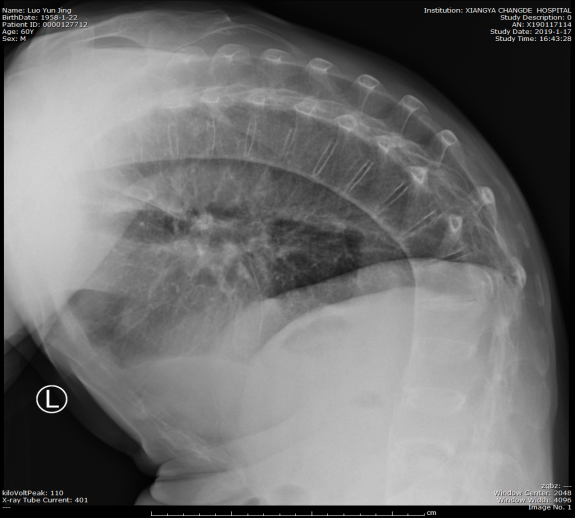

患者脊柱弯曲严重

经顿金庚教授详细为患者检查后,确诊为前列腺增生症并尿潴留。前列腺增生微创手术本是泌尿外科的一项常规手术,但罗大爷还有30余年的强直性脊柱炎病史,也就是俗称的“活僵尸”他的脊柱和双下肢僵直固定,脖子无法后仰、双下肢无法分开,这无疑给麻醉和手术增加了不小的难度。术前,麻醉手术部、泌尿外科经过了充分讨论后,为罗大爷量身定制了一套适合的手术方案。